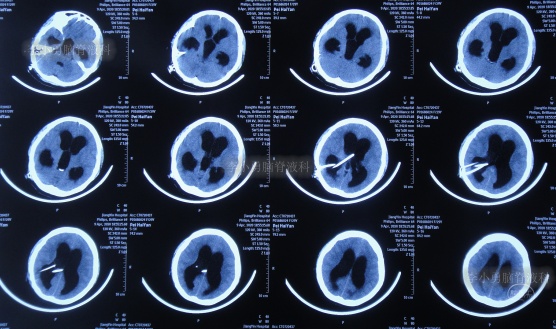

图-4:2006年8月23日头颅CT

第1次脑室腹腔分流术后8个月即2007年5月1日,再次出现头晕头痛,在江苏省江阴市某医院查头颅CT(图-5)后传给给予手术医生,医生考虑是分流管堵塞。

图-5:2007年5月1日头颅CT

因分流管堵塞,2007年5月2日(第1次脑室腹腔分流术后8个月),第2次住入给予手术的医院,2007年5月5日(入院后3天),术后例行查头颅CT(图-6)后,加做了脑室腹腔分流术,但保留了原脑室分流管。

图-6:2007年5月5日头颅CT

图-7:2007年5月6日头颅CT上海

第2次脑室腹腔分流术后3月余即2007年8月15日,查头颅CT示未见异常(图-8)。

图-8:2007年8月15日头颅CT